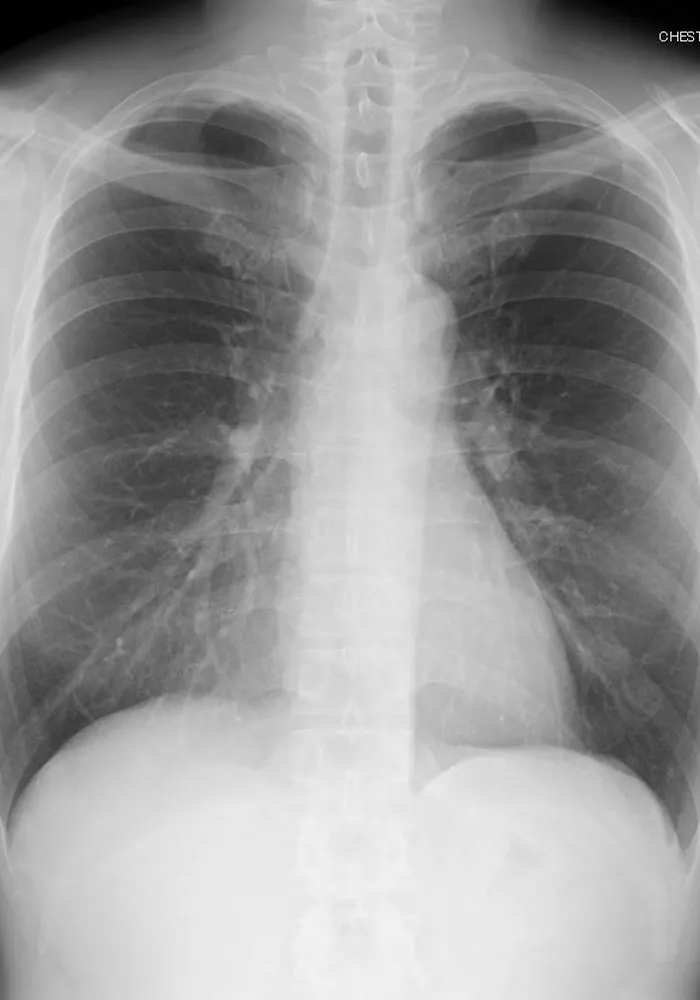

一般撮影

一般撮影は診断目的とする部分にX線を照射して撮影を行う検査です。X線は体内を通過する際に骨や筋肉、内臓などの組織により吸収される量が変化するので、透過したX線量の差を画像化したものがレントゲン写真となります。